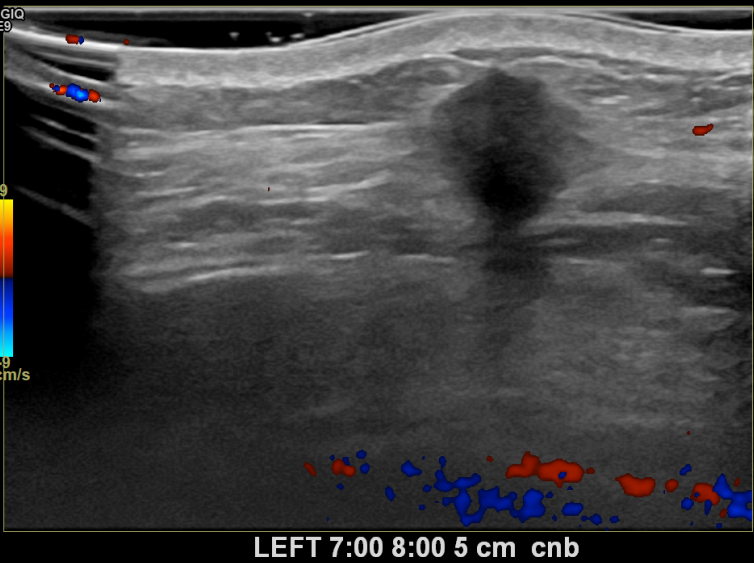

상기환자는 만져지는 멍울로 내원하신 30대중반 여성분으로 의심스러운 좌측혹

조직검사 시행해 침윤성암으로 진단되었습니다